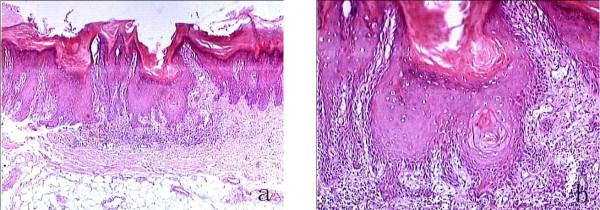

中国大陆地区快速进展性增殖性疣状白色角化病病例报告及病因学建议。

Case report of rapidly progressive proliferative verrucous leukoplakia and a proposal for aetiology in mainland China.

Proliferative verrucous leukoplakia (PVL) is a rare oral leukoplakia and has four features such as chronic proliferation, multiple occurrences, refractoriness to treatment and high rate of malignant transformation. As mentioned above, most PVL cases processed to malignancy over many years, sometimes 20 years. However, this report described a case of rapid progress, which had malignant transformation in a short period. Additionally, the aetiology of PVL was discussed and immunity was proposed as the possible cause.

增殖性疣状白斑(PVL)是一种罕见的口腔白斑病,具有慢性增殖、多发性、难治性和高恶性转化率等四个特征。如前所述,大多数 PVL 病例在多年后发生恶变,有时甚至长达 20 年。然而,本报告描述了一例快速进展的病例,其在短时间内发生了恶性转化。此外,还讨论了 PVL 的病因,并提出了免疫可能是其发病原因之一。